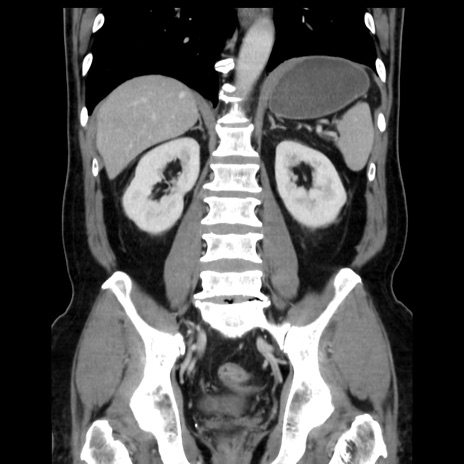

症例16(冠状断像)

【症例】 70歳代男性

【主訴】 腹痛、嘔吐

【現病歴】 約1ヶ月前より間欠的に腹痛と嘔吐あり、当院消化器内科を受診したところCTで多発する肝臓のLDAを指摘され、精査中であった。以降は消化器症状は安定していたが、2日前より嘔気と腹痛があり、同日より排便・排ガスが消失した。改善認めず、 本日、救急外来を受診した。

【データ】WBC 7200、CRP 0.77